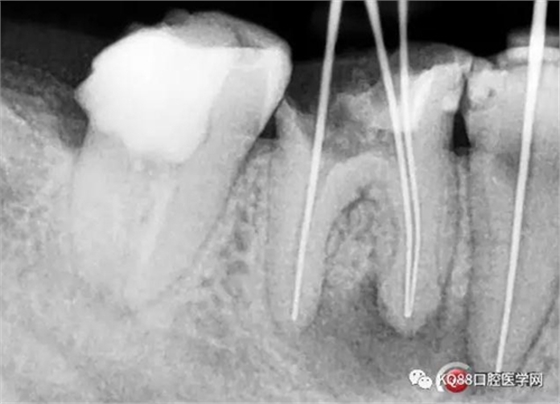

處理與結(jié)果:45局麻去髓,在確定工作長度時(shí)拍X線片顯示:46近中根尖周稀疏影,且邊緣呈淡薄云霧狀。

例2 45根管測量時(shí)X線片所見